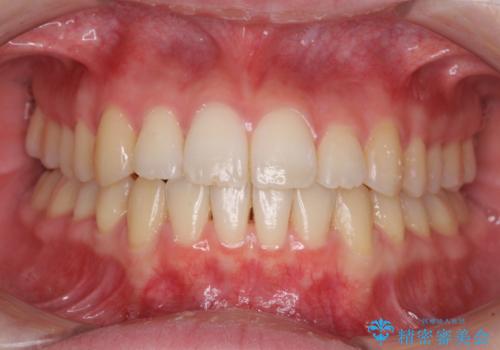

上下前歯の捻れが改善され、患者様には大変満足していただきました。